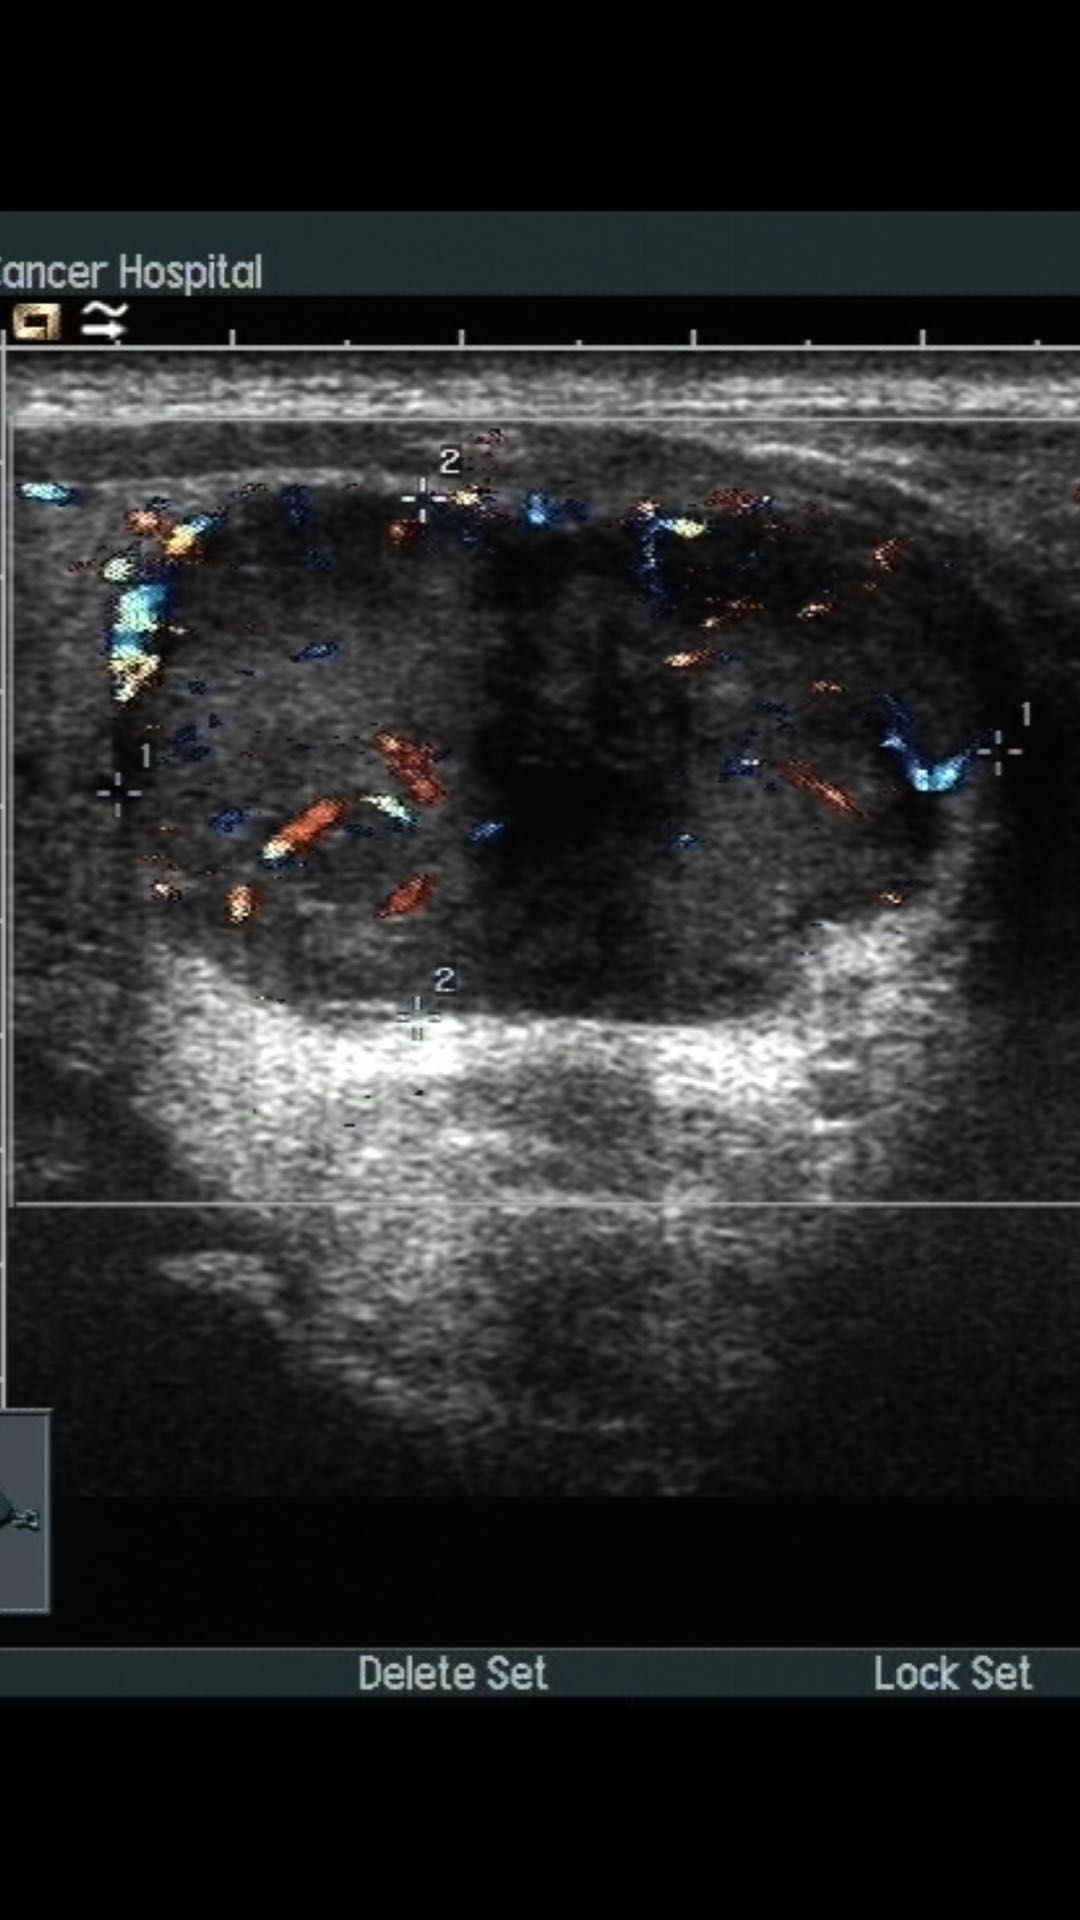

术前超声,可见甲状腺左叶结节,大小约2.9cm*1.2cm.边界清,形态规则.